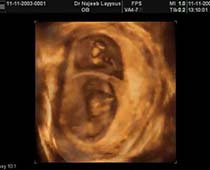

- Fetal Face Ultrasound Photos

- 3D Fetal Profile Ultrasound Scan Photos

- First Trimester Ultrasound Photos

- Multiple Pregnancy Ultrasound Photos

- The Clinical Advantages of 3D and 4D Ultrasound

- Definition and Features of Four Dimensional Ultrasound

- Uses of 4D Ultrasound scan

- The importance of 4D ultrasound imaging in pregnancy